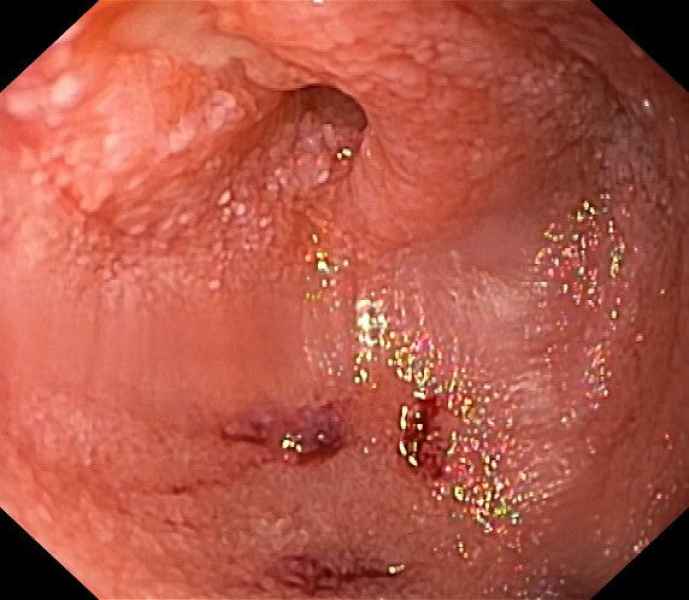

Widespread signs of an unexpected diagnosis

Fotografia